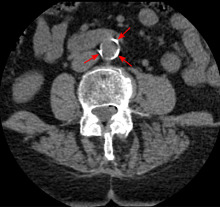

CT image of atherosclerosis of the abdominal aorta. Woman of 70 years old with hypertension and dyslipidemia.

Doppler ultrasound of right internal Carotid artery with calcified and non-calcified plaques showing less than 70% stenosis

Lumen stenosis that is greater than 75% was considered the hallmark of clinically significant disease in the past because recurring episodes of angina and abnormalities in stress tests are only detectable at that particular severity of stenosis. However, clinical trials have shown that only about 14% of clinically debilitating events occur at sites with more than 75% stenosis. The majority of cardiovascular events that involve sudden rupture of the atheroma plaque do not display any evident narrowing of the lumen. Thus, greater attention has been focused on "vulnerable plaque" from the late 1990s onwards.[69]